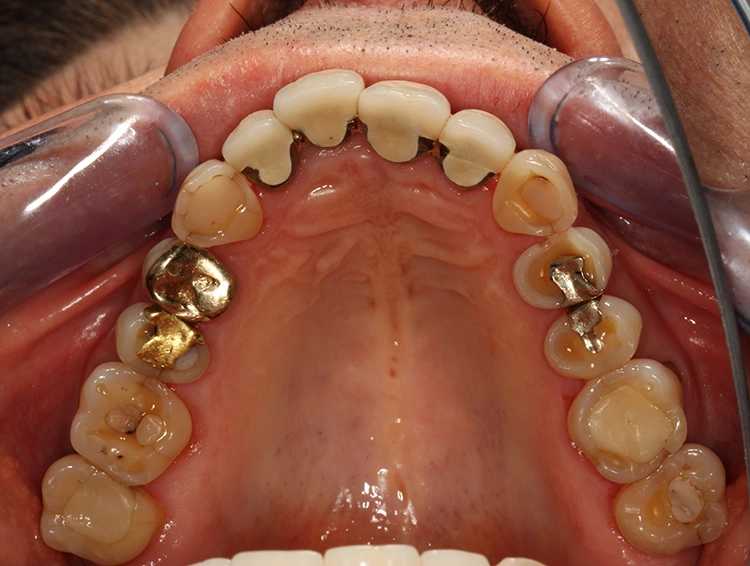

Dentalstatus: Es zeigen sich generelle Abrasionen, Attritionen und Erosionen im Ober- und Unterkiefer. Die ursprüngliche anatomische Kauflächenstruktur in den Seitenzahnbereichen ist durch die massiven erosions- und attritionsbedingten Zahnhartsubstanzverluste nicht mehr vorhanden (Tab. 2). Aufgrund der massiven Zahnschmelzverluste erscheint die Zahnfarbe insgesamt gelblicher. Der Patient wünscht sich im Rahmen der Rehabilitation in dieser Frage eine merkliche Verbesserung.

Egger/Wermuth/GrevenRote Ästhetik: Im Ober- und Unterkiefer zeigten sich generalisiert ausgedehnte Rezessionen mit bis zu 8 mm Attachmentverlust vor allem im Bereich der Eckzähne (Miller-Klasse III; Rezessionstyp [RT] 2 [69]. Das Band an keratinisierter Schleimhaut ist durchgehend vorhanden. Die Breite variiert im Eckzahnbereich von 1 mm bis zu 2 mm im Bereich der Unterkieferfrontzähne, der Prämolaren und Molaren (Abb. 1). Die fazialen Rezessionen sind mit approximalem röntgenologischem Attachmentverlust im koronalen Wurzeldrittel (Abb. 2) und Papillenverlust im Bereich zwischen den Kontaktpunkten und der approximalen Schmelz-Zement-Grenze assoziiert (Abb. 1). Der Patient verfügt über eine schmal geformte Oberlippe. Die Lachlinie verläuft mittelhoch (Abb. 3).

Parodontale Gesundheit bei Attachmentverlust, Bruxismus, Erosion. Abbildung 1 sowie 6 bis 9 zeigen den Anfangsbefund als intraoralen Fotostatus.*